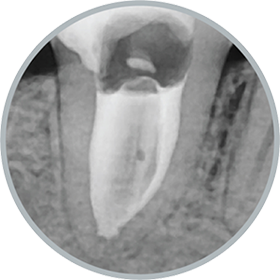

Hard tissue formation

Endoseal MTA demonstrates excellent performance in promoting the formation of surrounding periapical tissues in infected teeth.

Its superior capability in tissue regeneration has been confirmed through various genetic studies.